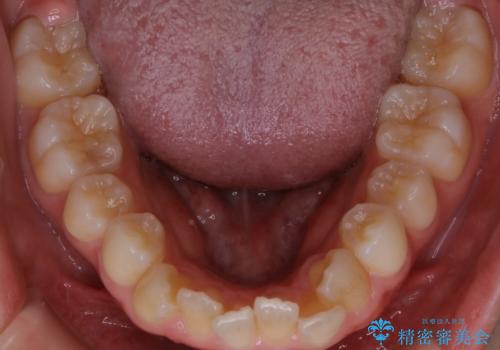

初診時の歯並びの状態としては、上下ともに全体に及ぶの中等度のがたつき(叢生)があり、全特に左上の前歯は1本だけ引っ込んでいる状態でした。

抜歯は行わず上顎の奥のスペースを利用して歯をスライドする方法の他に歯列弓の拡大やディスキング(歯と歯の間の隙間を作る処置)を行い叢生を改善しました。

歯の大きさの不揃いが原因の正中のズレは、ディスキング量を調整することで合わせています。